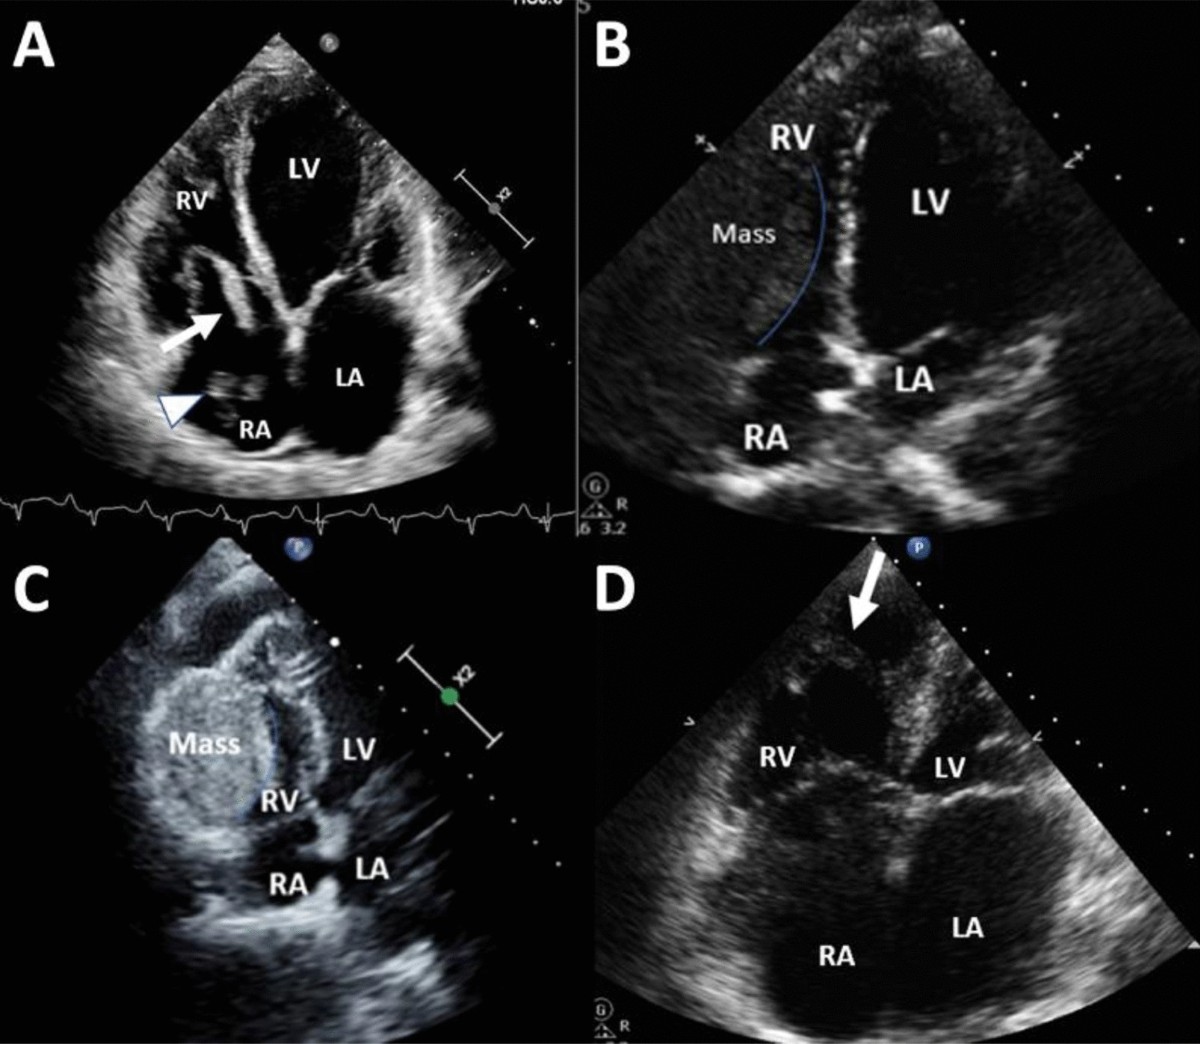

» Interpreting cardiac echo results (98) 사진

Interpreting cardiac echo results (98) 사진